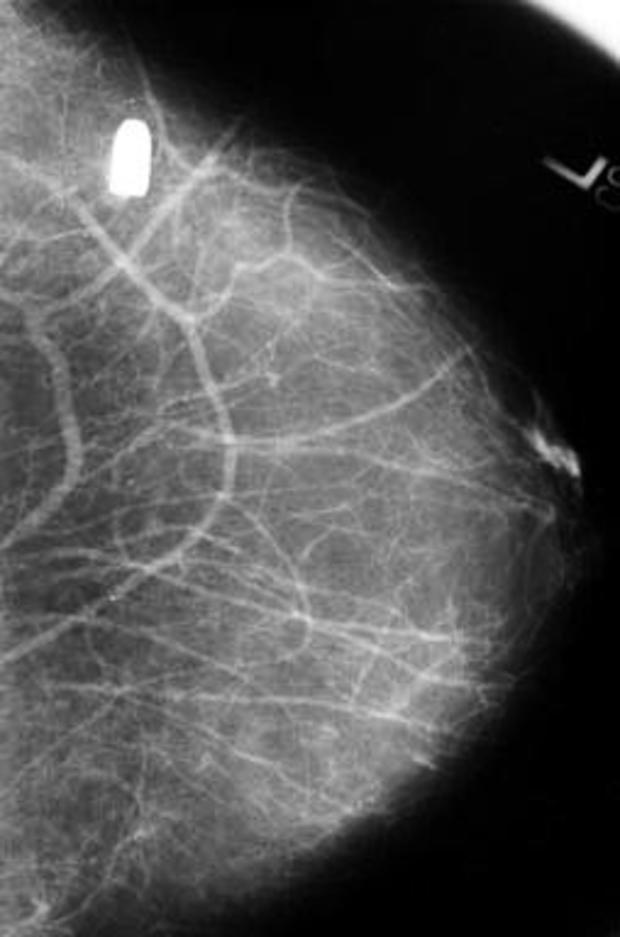

Not-so-routine mammogram

This bullet, lodged in a woman's left breast, was discovered during a routine mammogram years after she had been shot. It didn't seem to pose any threat to her health, so doctors left it in place. She told doctors that the man who shot her was dead.